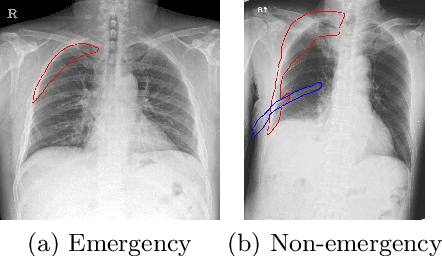

Abstract:Finding diseases from an X-ray image is an important yet highly challenging task. Current methods for solving this task exploit various characteristics of the chest X-ray image, but one of the most important characteristics is still missing: the necessity of comparison between related regions in an image. In this paper, we present Attend-and-Compare Module (ACM) for capturing the difference between an object of interest and its corresponding context. We show that explicit difference modeling can be very helpful in tasks that require direct comparison between locations from afar. This module can be plugged into existing deep learning models. For evaluation, we apply our module to three chest X-ray recognition tasks and COCO object detection & segmentation tasks and observe consistent improvements across tasks. The code is available at https://github.com/mk-minchul/attend-and-compare.